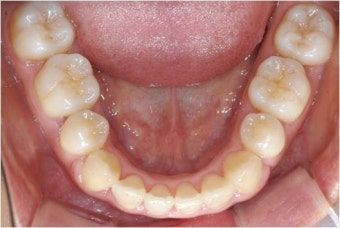

잇몸은 치아의 뿌리와 그것을 감싸는 치조골(턱뼈 일부)을 지지하는 구조입니다.

하지만 구강 내 세균인 치태(Plaque, 플라크)가 치아 표면에 쌓이면서 염증이 시작되며, 이 치태는 단단해지면 스케일링 없이는 제거가 불가능합니다.

증상이 심해지면 치아 사이에 음식물이 끼고, 치아가 흔들리며 심한 경우 치아 발치로 이어질 수 있습니다.

- 충치보다 잇몸병이 치아 상실의 주요 원인임을 인식하고, 적극적인 관리가 필요합니다.

- 올바른 칫솔질 & 치실 사용법 익히기 (하루 2~3회, 식후 3분 이내)

- 잇몸 출혈, 색 변화, 입냄새에 주의